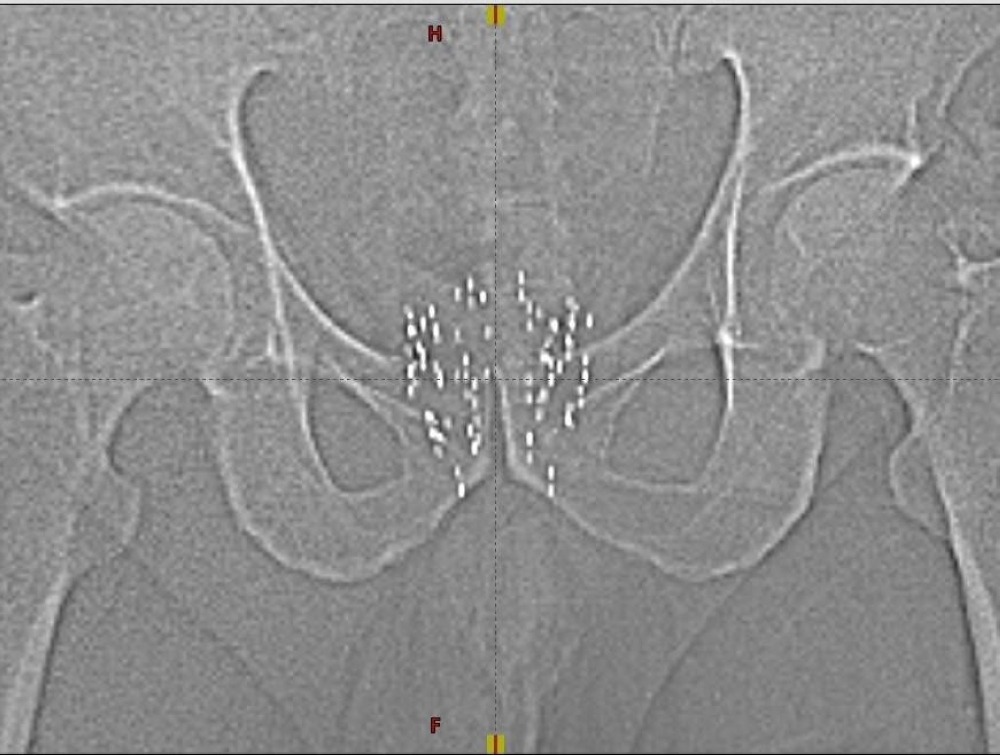

The operation was conducted by Dr Nadeem Pervis a senior consultant radiation oncologist, with a team of specialized doctors, medical physicists, anaesthetists, therapists and nurses. The operation was 2 hours long, where 82 radioactive seeds of Iodine 125 were implanted in and around the prostate.

The brachytherapy procedure involves insertion of needles containing radioactive seeds smaller than grains of rice, these seeds release radiation locally over a number of days, destroying the cancer cells stopping them from dividing and growing.